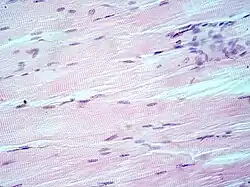

Hematoxylin principally colors the nuclei of cells blue or dark-purple,[6][15][14] along with a few other tissues, such as keratohyalin granules and calcified material. Eosin stains the cytoplasm and some other structures including extracellular matrix such as collagen[5][7][14] in up to five shades of pink.[8] The eosinophilic (substances that are stained by eosin)[5] structures are generally composed of intracellular or extracellular proteins. The Lewy bodies and Mallory bodies are examples of eosinophilic structures. Most of the cytoplasm is eosinophilic and is rendered pink.[10][15] Red blood cells are stained intensely red.

Lung tissue taken from an emphysema patient. Cell nuclei (blue-purple), red blood cells (bright red), other cell bodies and extracellular material (pink), and air spaces (white).- Muscle tissue, cell nuclei (blue-purple), cell body (pink)